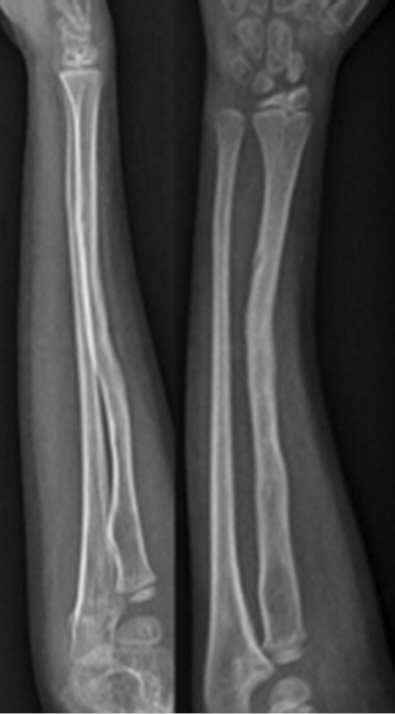

В декабре 2014 г. в отделение неотложной помощи поступил 4-летний мальчик после травмы правого предплечья с деформацией, болью и потерей функций, но без раны и без нейроваскулярной недостаточности. Установлен диагноз: «дистальный диафизарный перелом правой лучевой кости». Сломанная конечность была иммобилизована гипсовой повязкой. В январе 2015 г. появились признаки консолидации и гипс сняли. Через месяц после новой незначительной травмы пациент снова поступил в отделение неотложной помощи с диагнозом повторного перелома, но в этом случае у него был выявлен перелом со смещением дистальной трети правой лучевой кости (рис. 1).

Рис. 1. Повторный перелом через 3 мес.

При хирургическом лечении были использованы спицы Киршнера, но во время операции произошло осложнение в виде ятрогенного продольного перелома, который был синтезирован проволочным серкляжем. Примерно через 3 мес. после операции, хотя на рентгенограмме были незначительные признаки консолидации кости, металл был удален и предплечье было иммобилизовано новой повязкой (рис. 2).

Рис. 2. На рентгенограмме незначительные признаки консолидации кости, но металл был удален и предплечье иммобилизовано новой гипсовой повязкой